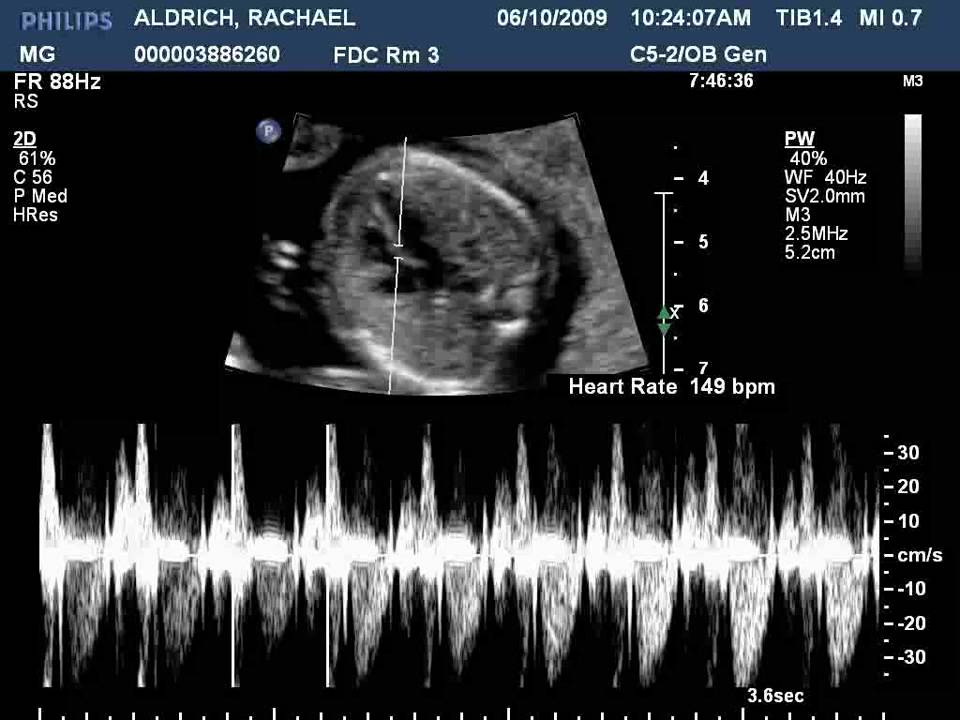

The heartbeat of a developing baby is a remarkable event that signifies the beginning of life. The heart is one of the first organs to develop in the fetus, and its rhythmic beating is a clear sign of a healthy pregnancy. The sound of a baby’s heartbeat can often be detected through an ultrasound as early as six weeks gestation.